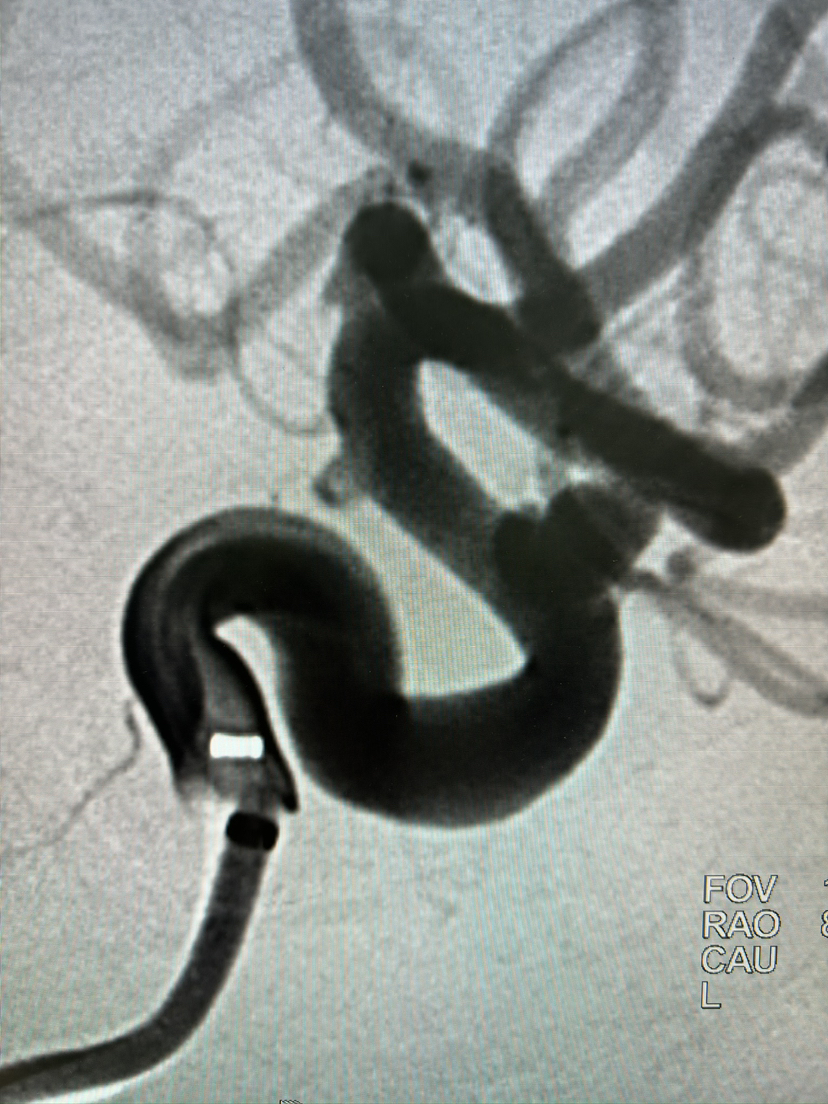

FRED血流导向密网支架栓塞眼动脉动脉瘤

#FRED®21 & FRED®27 血流导向密网支架

密网支架

动脉瘤

眼动脉